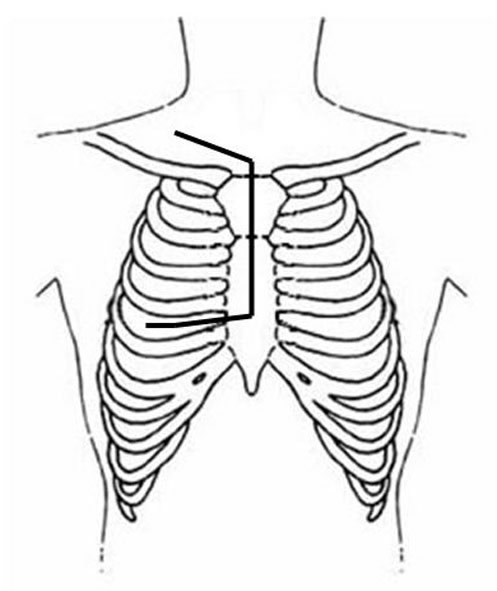

Incision

The patient is placed in the lateral decubitus position, with the arm over the head, exposing the axilla, scapular region, and neck. The incision starts anteriorly, allowing exploration of the chest cavity (usually through the fourth/fifth interspace) to assess the resectability. The extension of the tumor on the thoracic chest wall, thoracic inlet, lung, and mediastinum should be assessed. The incision is then extended posteriorly around the tip of the scapula and vertically upward between the spinous processes and posterior edge of the scapula, up to C7. The division of various muscle layers starts from the latissimus dorsi and trapezius to expose and subsequently divide the serratus anterior, rhomboidius major and minor, and levator scapulae muscles (Figure 5; Video 1). The rhomboid muscles insert into the medial border of the scapula, and care should be taken to avoid injuring the dorsal scapular nerve and satellite scapular artery, which run down the medial border of the scapula. A Fruchaud scapular retractor is used to elevate the scapula and expose the apex of the chest cage. The serratus posterior superior muscle is divided at its insertion on the second to fifth ribs, and the flap is preserved for later use (Figure 6; Video 2).